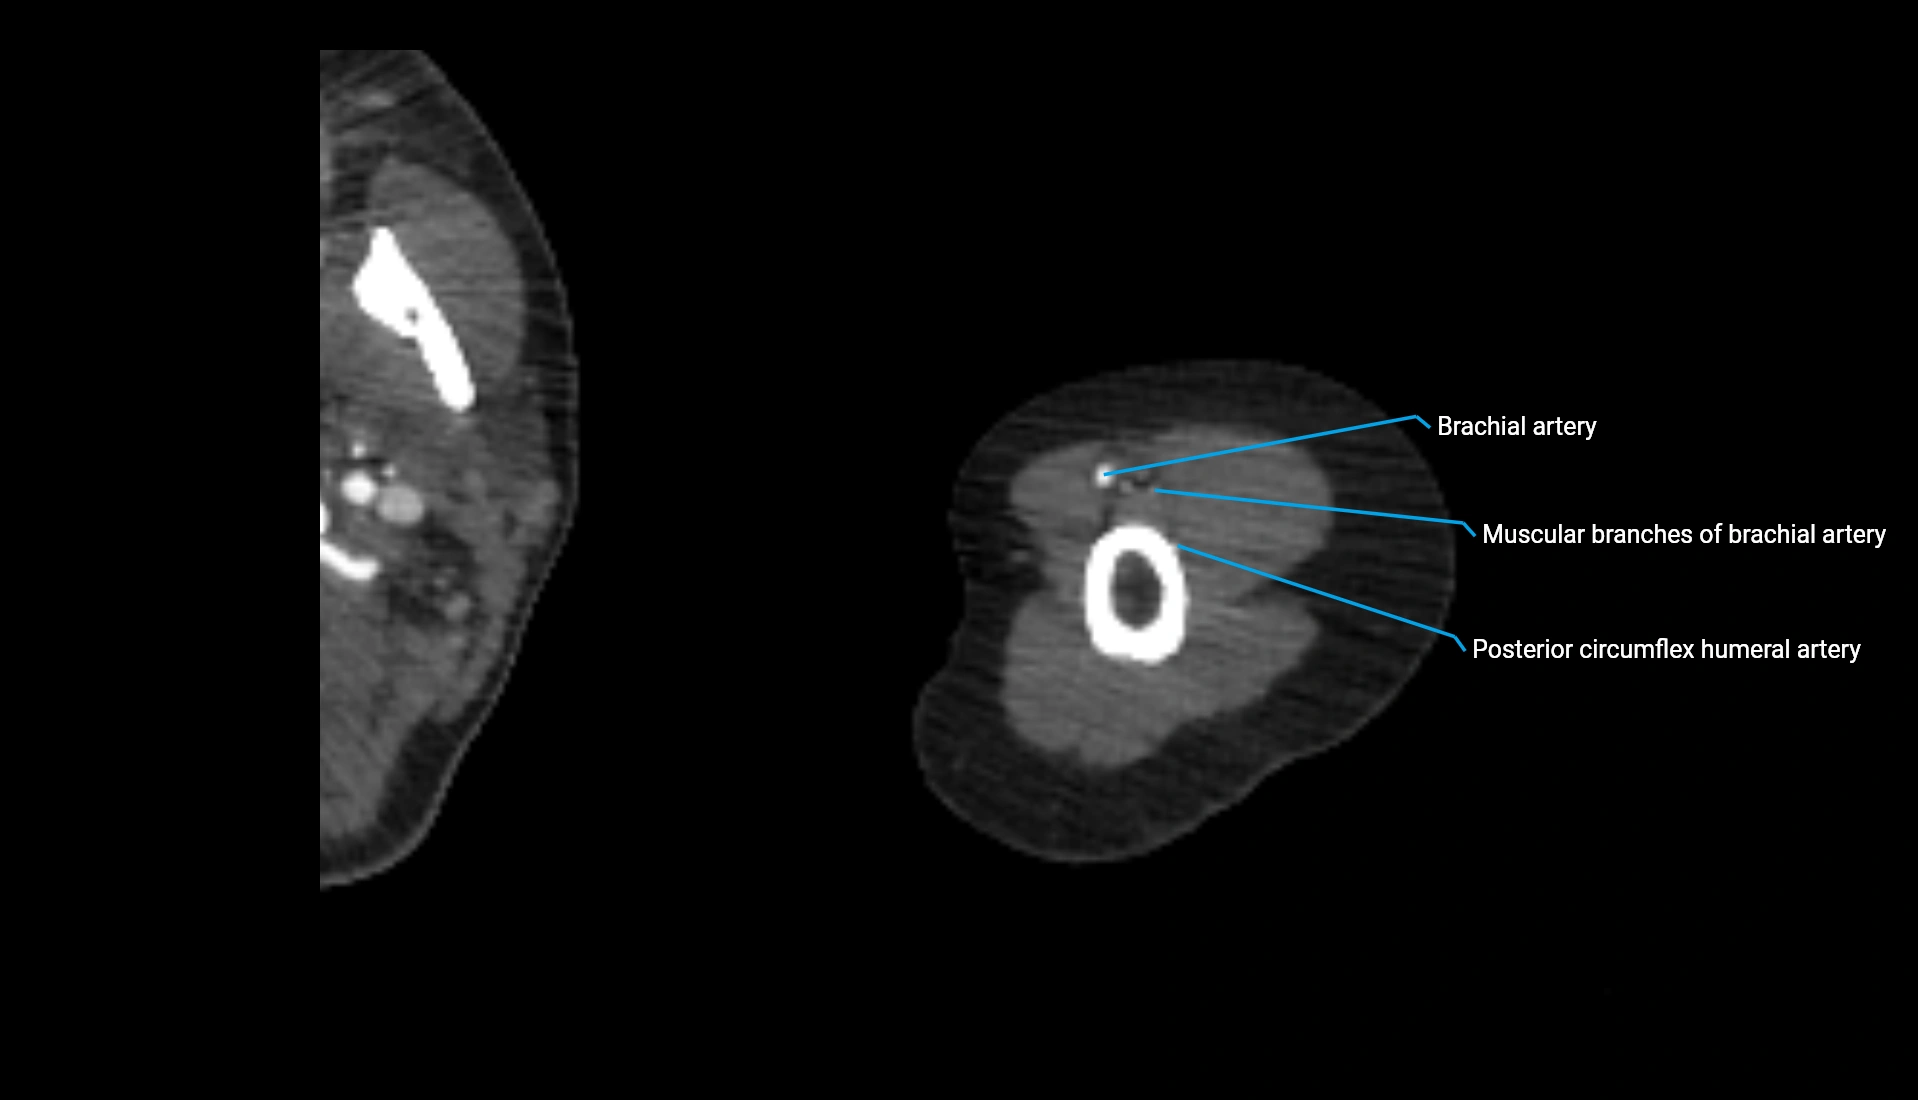

T2-weighted images:

• Cortex: Dark

• Marrow: Bright (fat + fluid sensitivity)

• Cartilage: Intermediate-to-brightly outlined, allowing evaluation of thickness

• Joint fluid: Bright

• Distinct visualization of the radiocapitellar interface